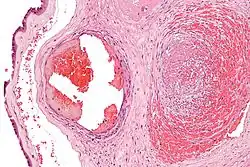

Micrograph showing fibrin (dark pink amorphous material) in a blocked vein surrounded by extravasated red blood cells (right of image). An artery (left of image) and the amnion (far left of image) is also seen. Placenta in a case of fetal thrombotic vasculopathy. H&E stain.